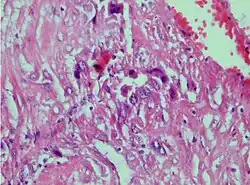

Photomicrograph showing proliferating intermediate trophoblast with scarce cytotophoblastic and syncytiotrophoblastic elements

A placental site trophoblastic tumor is a monophasic neoplasm of the implantation site intermediate trophoblast, and usually a benign lesion, which comprises less than 2% of all gestational trophoblastic proliferations. Preceding conditions include molar pregnancy (5%). Compared to choriocarcinoma or invasive mole, hemorrhage is less conspicuous and serum β-HCG level is low, making early diagnosis difficult.